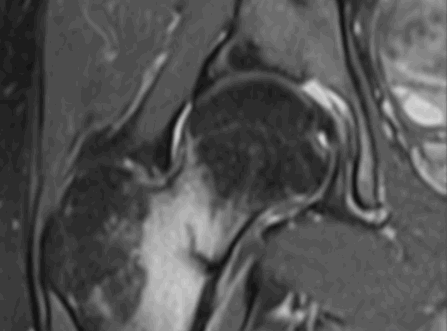

Аваскулярный некроз головки бедра.

Вид указанной патологии на МРТ, изменения соответствуют 2 стадии

К развитию аваскулярного некроза приводит длительное нарушение питания тазобедренного сустава на фоне загустевания крови, тромбообразования, сдавления, скручивания сосудов. В костной ткани при ишемии создаются пустоты, приводящие к деформации, отслойке хряща. Клинические проявления неспецифичны, что вызывает трудности в постановке диагноза. Провоцирующих факторов множество:

воздействие ионизирующего облучения и пр.

Ранние изменения не видны при рентгенографии, ультразвуковом исследовании. МРТ тазобедренного сустава - один из эффективных способов определить болезнь на начальной стадии.